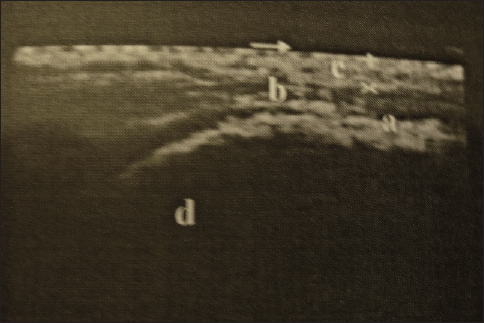

Diagnostic imaging by radiographic examination was limited to identifying overriding thoracic dorsal vertebral spinous processes using an output of 20 mA at 90 kV within 0.1 second. However, most projections suffer from superimposition of the lungs and poor resolution. Ultrasonographic examination of the thoracolumbar dorsal spines and sacroiliac region revealed 30 cases with sacroiliac pain or injuries with heterogenic echogenicity and thickening of the dorsal sacroiliac ligament, 16 cases with dorsal spinous desmopathy, and 8 cases with echogenic changes of longissimus dorsi aponeurosis (Fig. 5).

Fig. 5. Longitudinal ultrasonography of the sacroiliac region showing sacroiliac desmopathy (a-sacroiliac enthesophytosis, b-longissimus dorsi tendon, c-gluteal fascia, and d-sacral tuber).

In the present study, ultrasonography of the interspinous and sacroiliac ligament was helpful in the diagnosis of 30 cases (40%) being diagnosed with sacro-iliac desmopathy. Furthermore, intraspinous or sacroiliac, local analgesic injections were considered effective diagnostic tools. Here, it is important to pay considerable attention to this joint during the examination as it may be the origin of the problem. These results are consistent with those of other studies (Engeli and Haussler, 2011; Dyson and Murray, 2003).